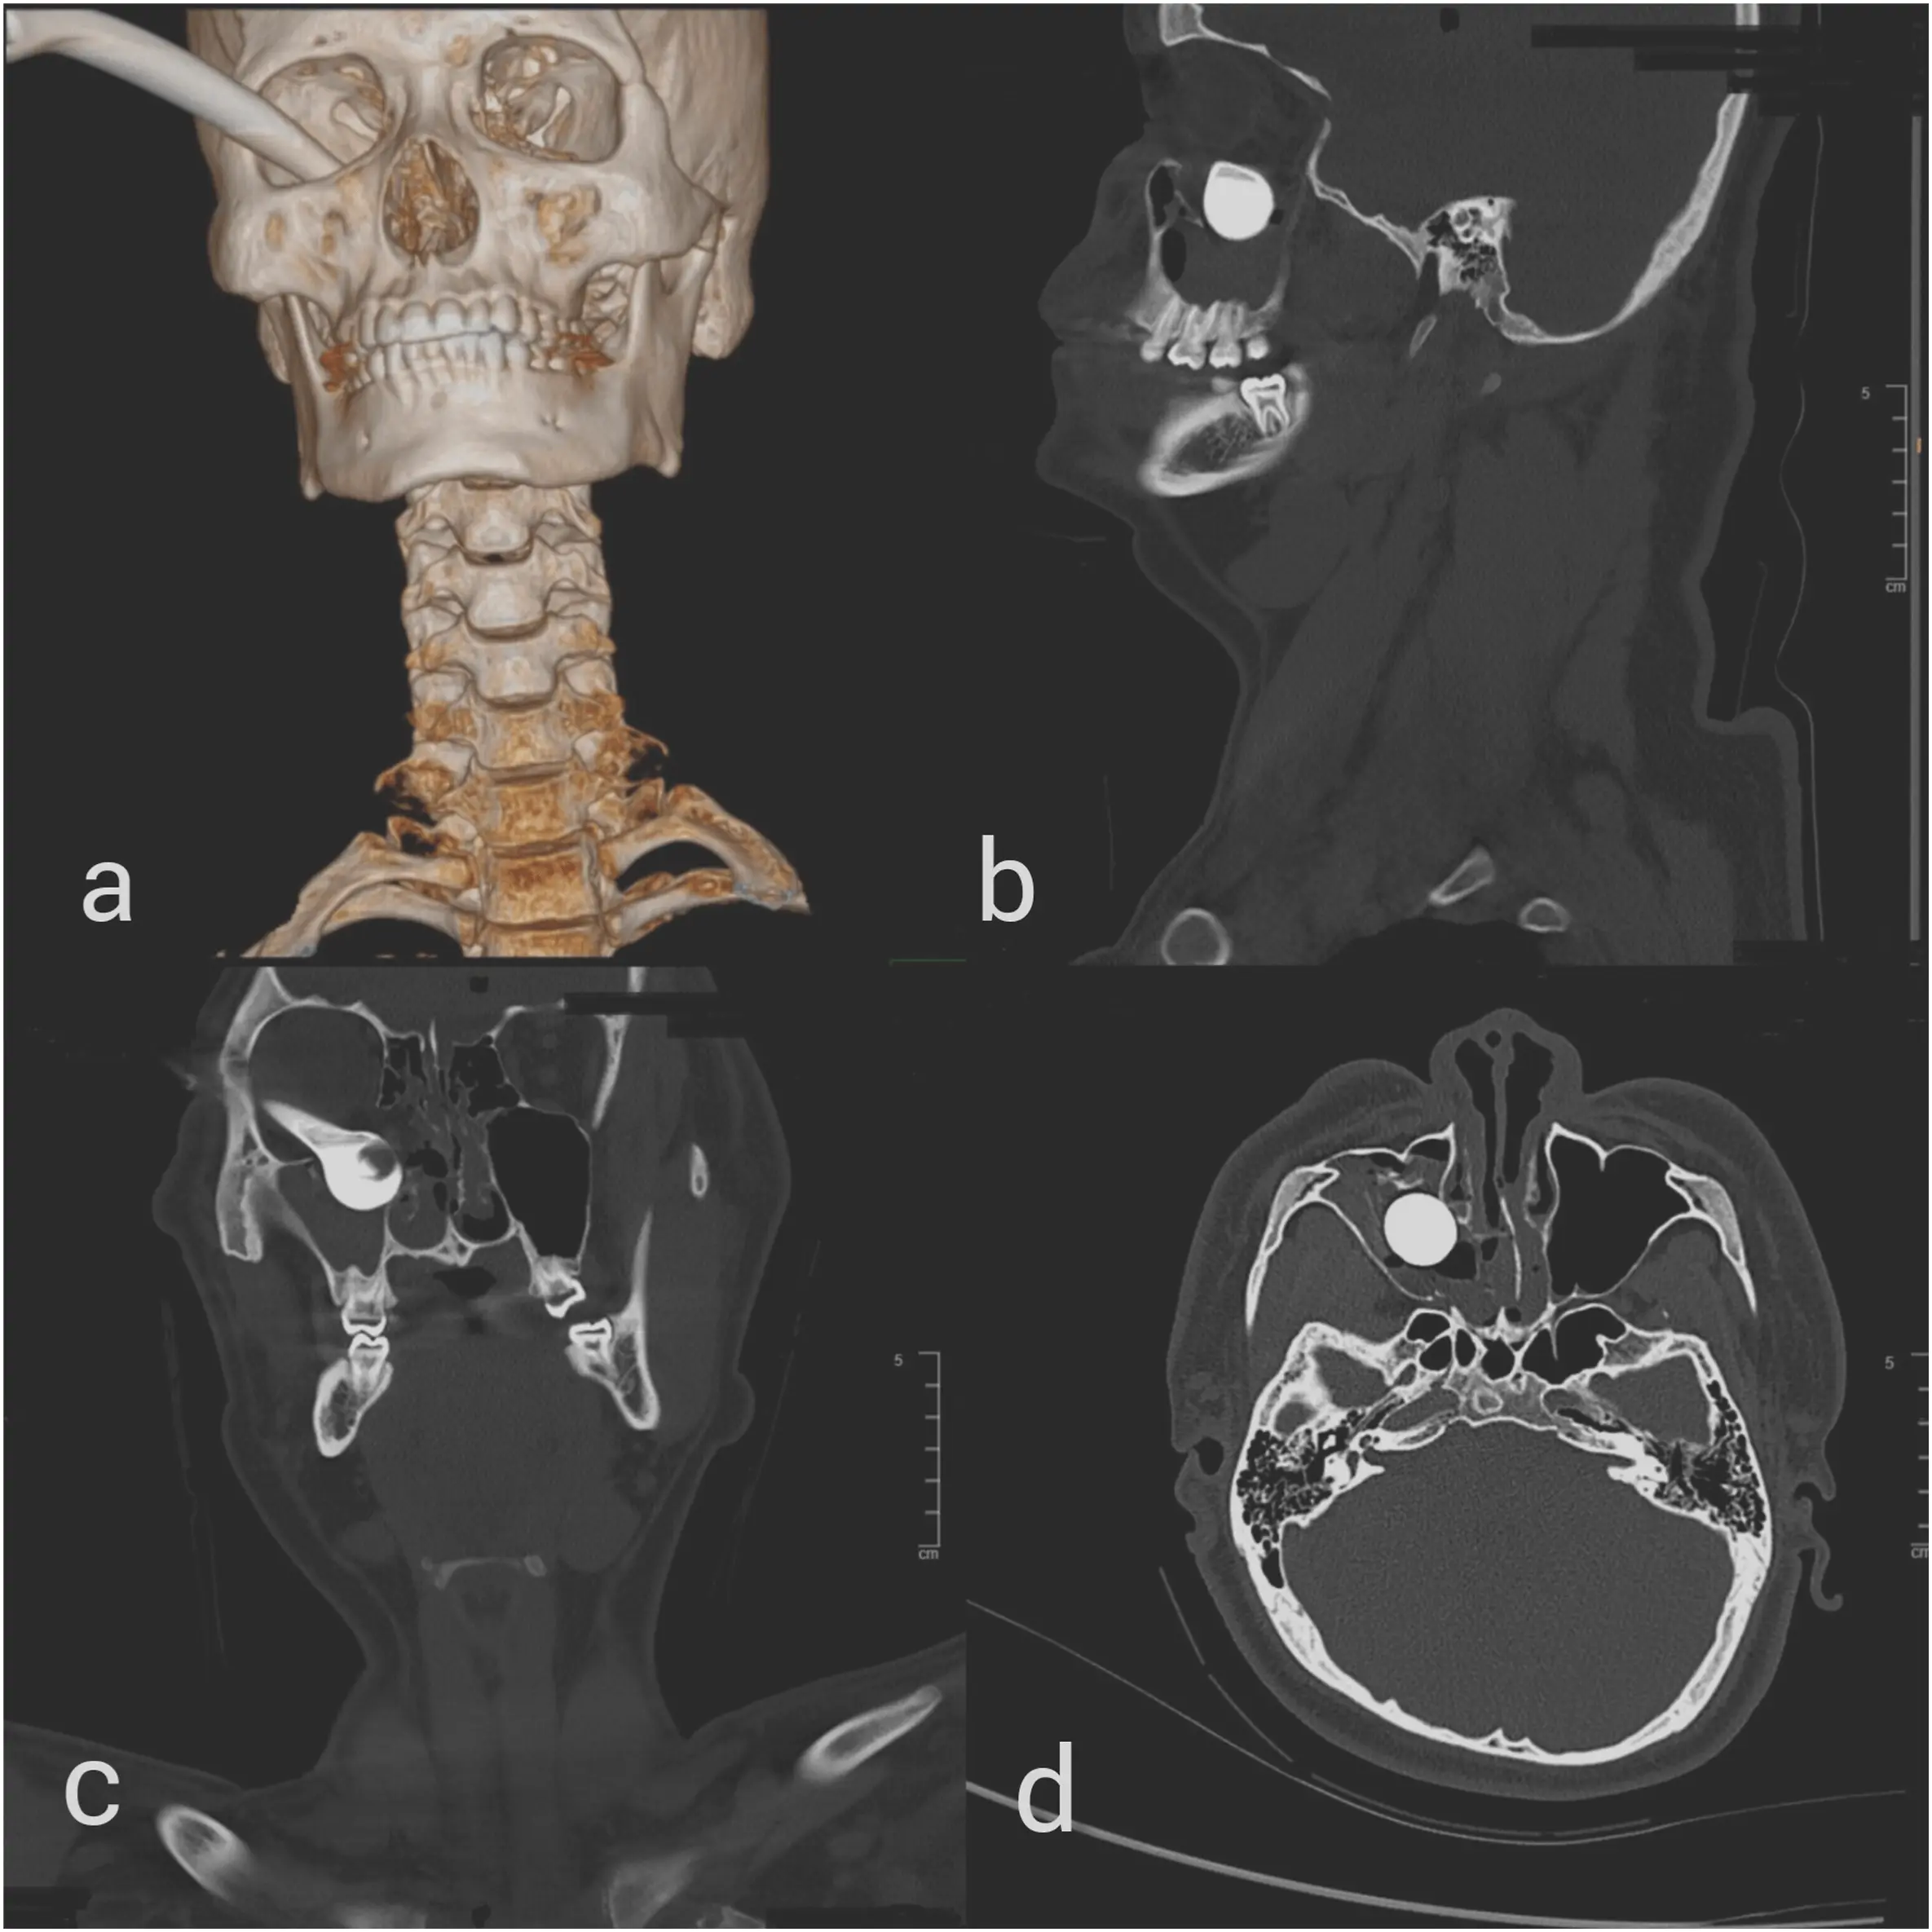

Si les scanners consécutifs à l'accident peuvent paraître impressionnants, les soignants se sont pourtant montrés rassurants. En réalité, le levier du frein avait manqué le globe oculaire et s'était logé quelques millimètres plus bas, dans la cavité orbitaire de l'oeil droit du pauvre jeune homme, occasionnant plusieurs fractures.

Fracture orbitale, douleurs et trouble cardiaque

Difficile dans une telle situation d'espérer une issue favorable pour l'oeil ou la vision du malheureux. Pourtant, malgré la fracture orbitale dont souffrait leur patient, ainsi que d'évidentes douleurs et rougeurs au niveau de l'oeil, les médecins se sont rendus compte qu'il pouvait toujours utiliser correctement globe oculaire, même plusieurs heures après l'accident.

Le levier avait miraculeusement évité sa pupille et ses nerfs vitaux, empêchant des dommages nerveux à long terme. Les médecins lui ont toutefois diagnostiqué un réflexe oculocardiaque, un trouble du rythme cardiaque causé par la compression du globe oculaire, selon l'Académie de médecine. Le patient a donc été conduit au service d'urgence de l'hôpital, où l'équipe médicale est parvenue à lui retirer le frein, avant de suturer la plaie et de recoudre la paupière endommagée.